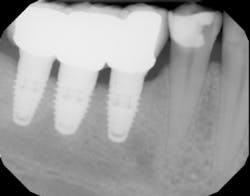

This technique should be used as standard practice when restoring caries adjacent to dental implants (figure 3).

Figure 3: Deep caries adjacent to dental implants is complicated by a deep sulcus. The two-matrix system margin-elevation technique is used to restore proper contour, emergence profile, and contact.